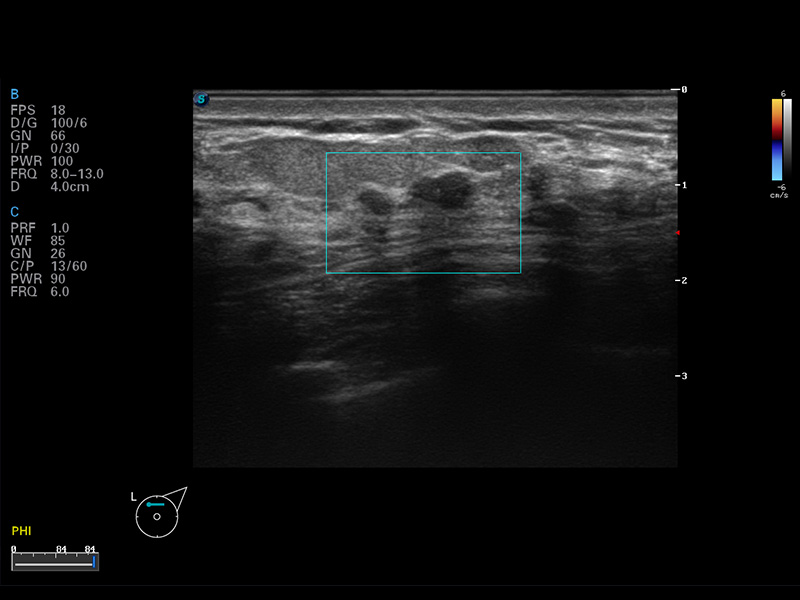

S8 EXP便携式彩色多普勒超声诊断仪是银河集团官网研发的高端全身应用型便携彩超。高通道的VIS平台融合可视化(Visual)、智能化(Intelligent)和人性化(Smart)的特点,配以银河集团官网自主研发生产的探头大家族,使您能够快速、准确的获得病人信息,提高工作效率的同时减轻疲劳。

μ-Scan微米成像

空间复合成像